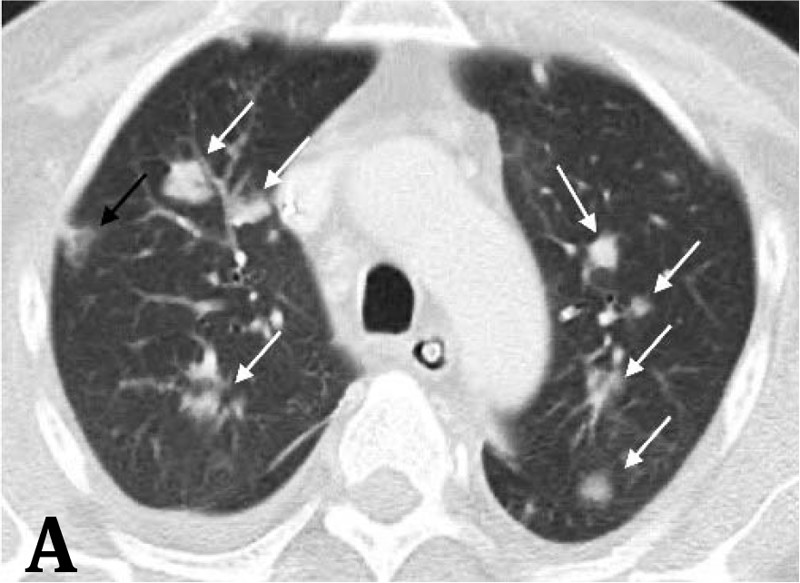

Haga usted el diagnóstico. Parte 1

Haga usted el diagnóstico. Parte 2